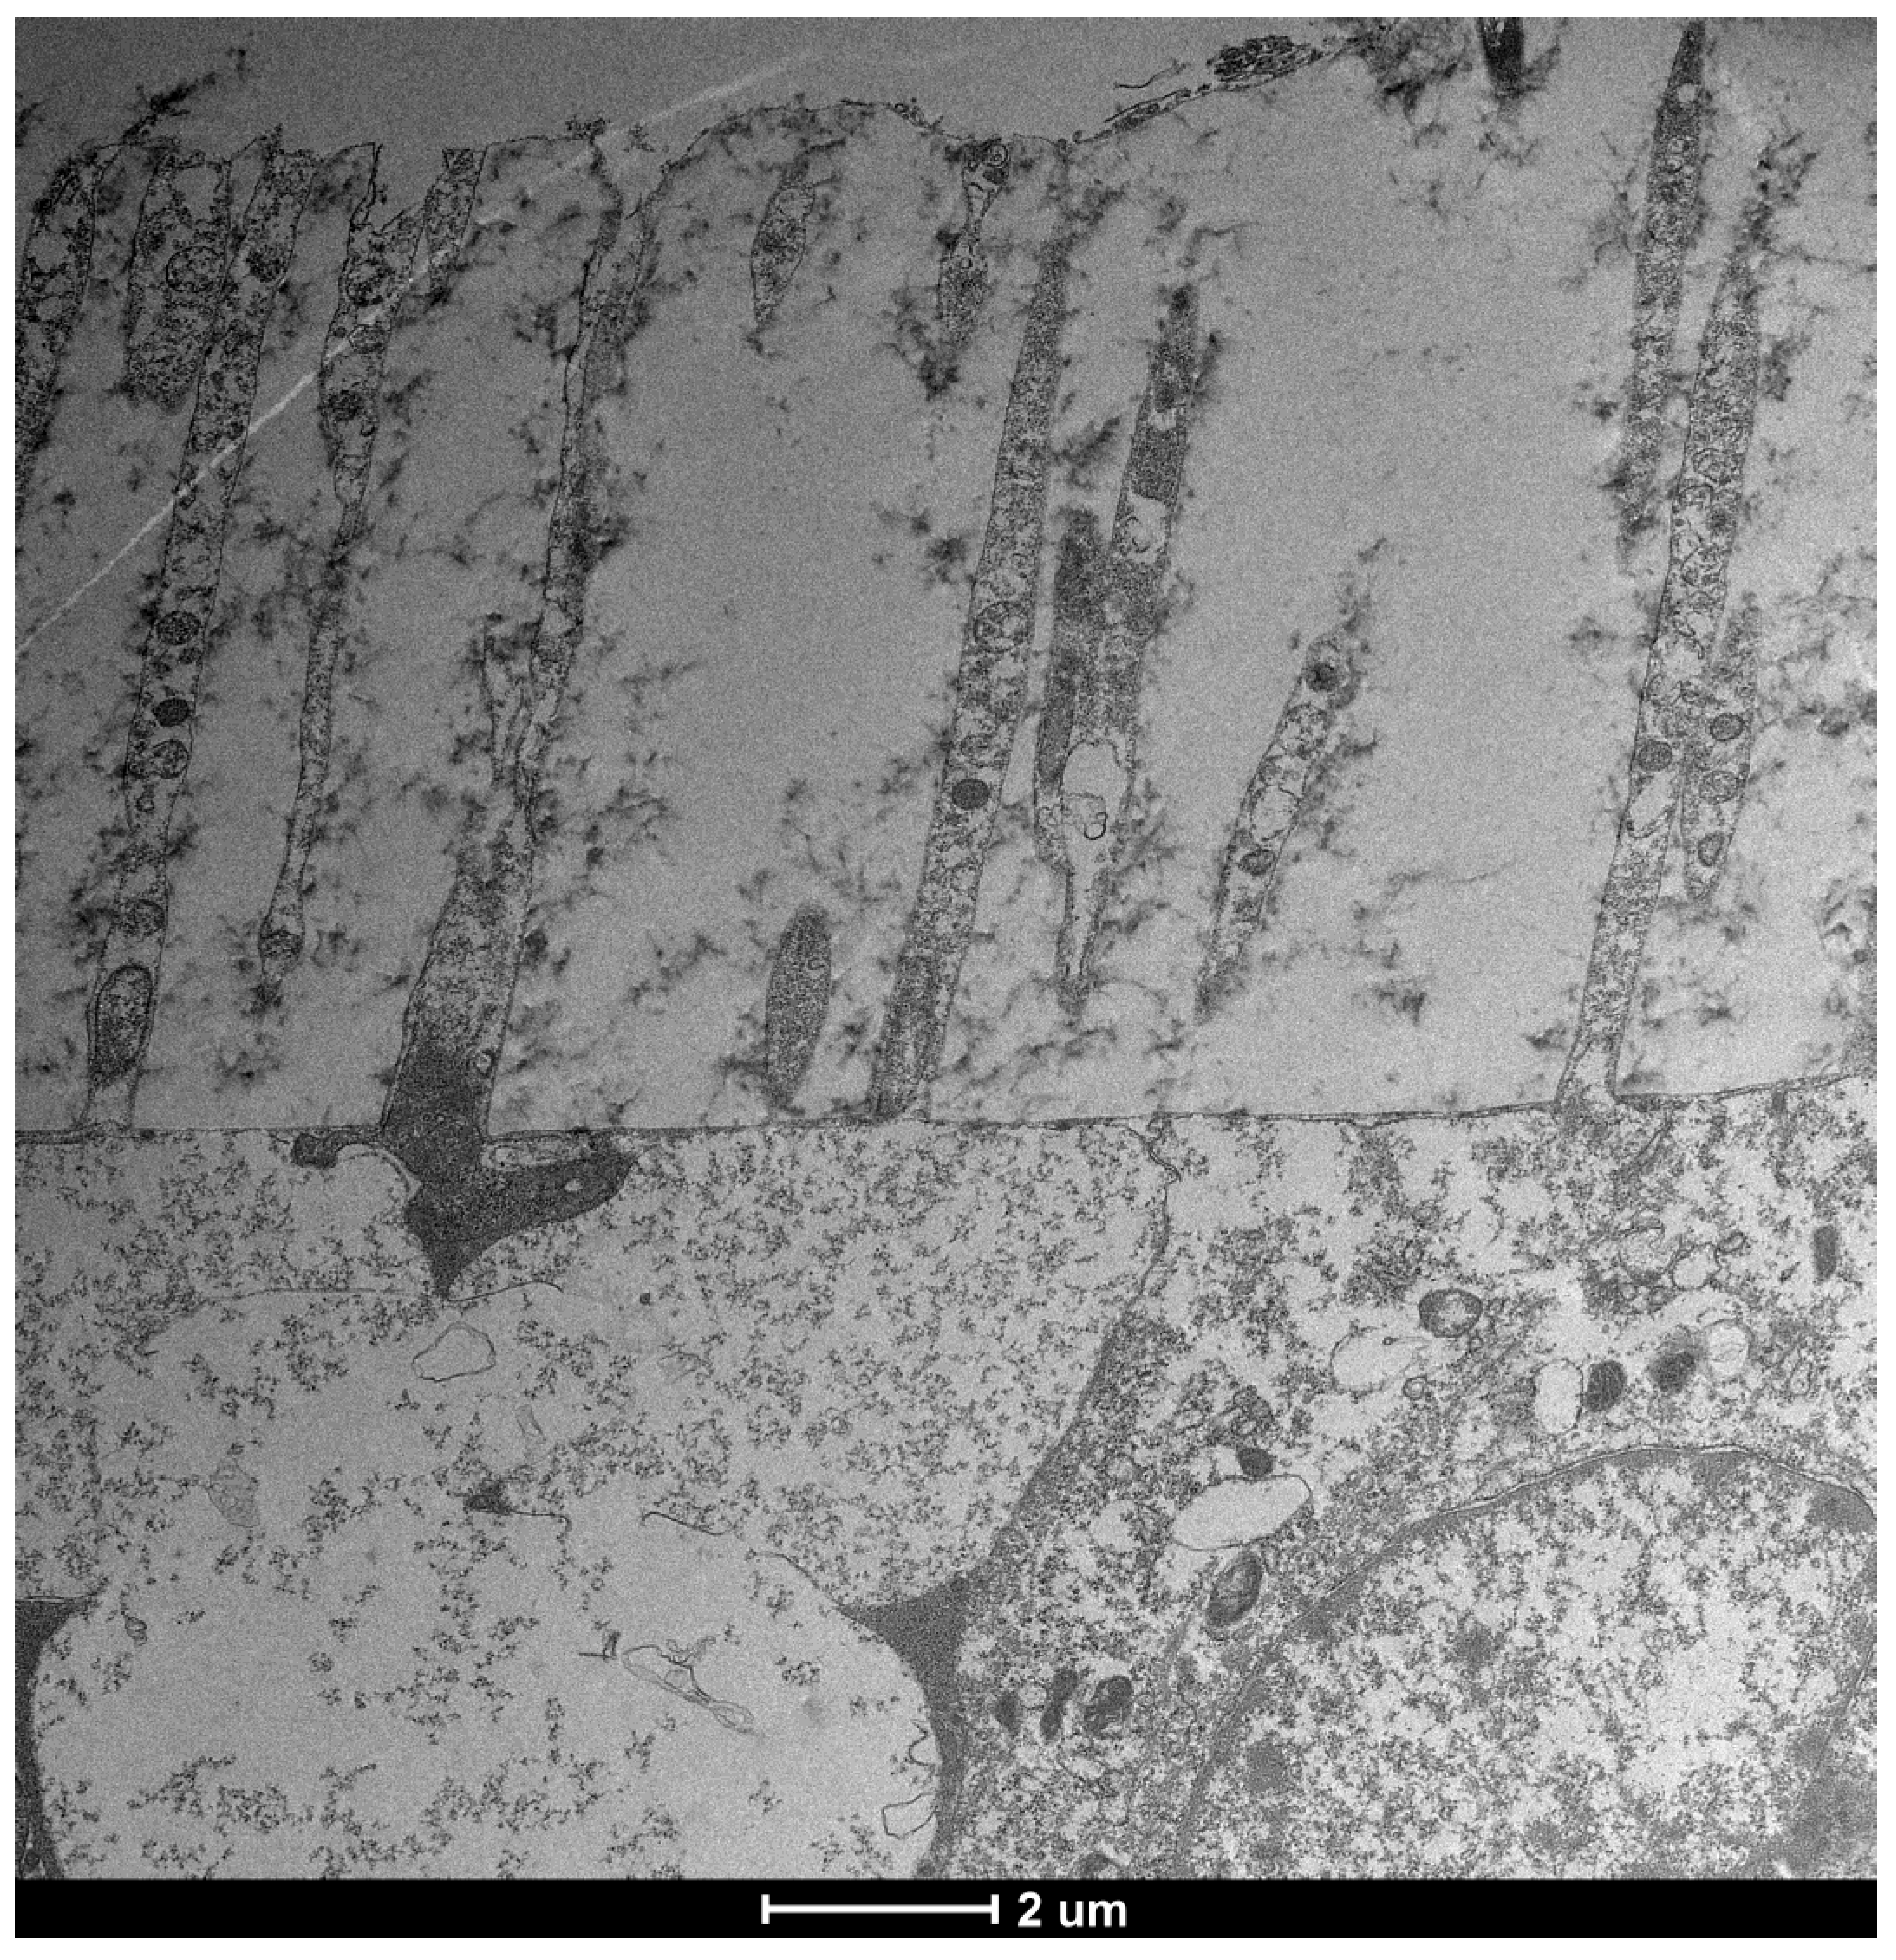

| TEM Evaluation Table | ||||

| Grade 0 | Grade 1 | Grade 2 | Grade 3 | Grade 4 |

| Presence of glicocalyx and presence vescicular transport | Reduction of Glicocalyx and presence of vescicular transport | Absence of glicocalyx and reduction of vescicular transport | No glicocalyx, No vescicular transport, Reduction of lenght of microvilli | flattening of the plasma membrane, absence of exchange with the outside |